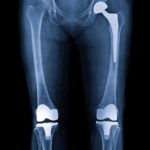

Hesitant About Joint Replacement? Don’t Be – You’re in Good Company

Arthroplasty, a surgery to replace a damaged joint with a prosthesis, is now performed on a daily basis throughout the United States. In fact, there are well over 1 million arthroplasties performed each year in the nation according to the National Institutes of Health and that number is expected to grow to 4 million by […]